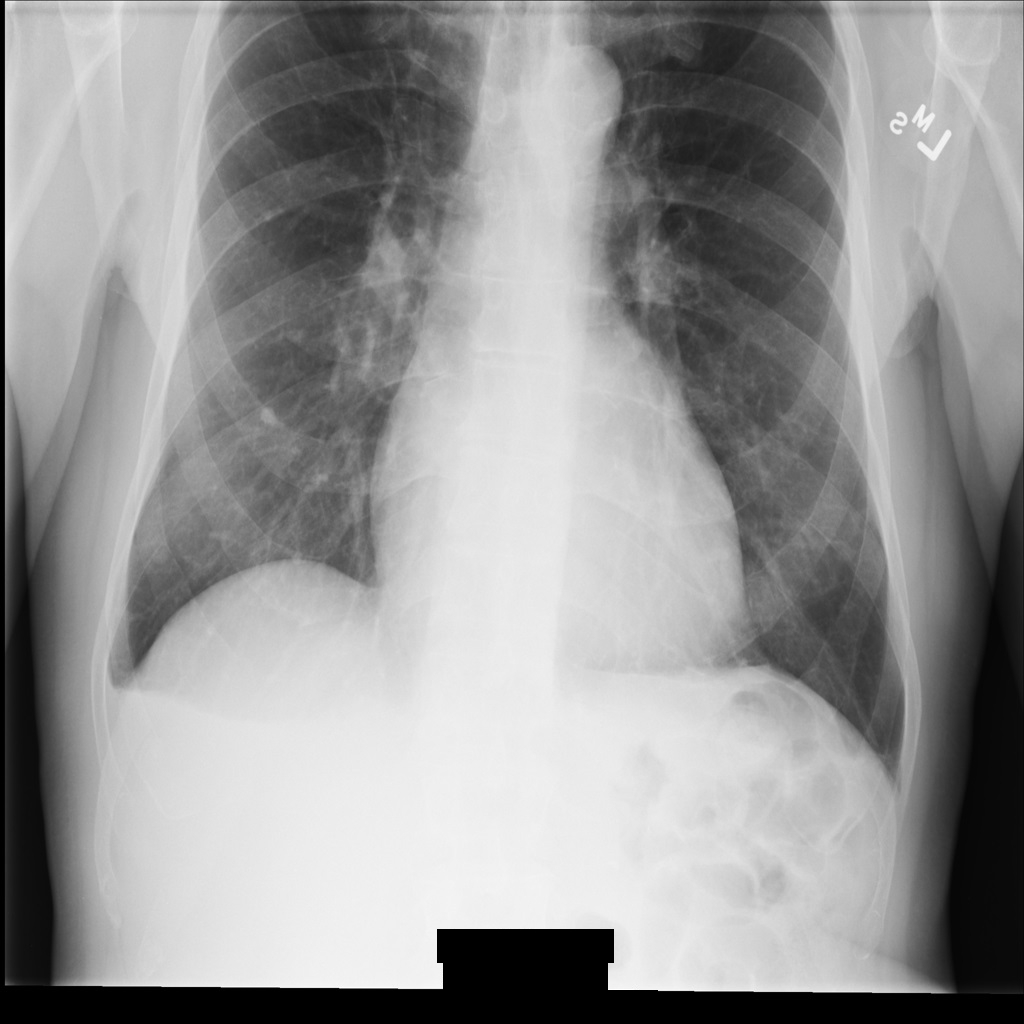

Beispielbild

Einige Beispiele auf dieser Seite enthalten eine Ausgabe des de-identifizierten Bildes. In jedem Beispiel wird das folgende Originalbild als Eingabe verwendet. Sie können das Ausgabebild jedes De-Identifizierungsvorgangs mit diesem Originalbild vergleichen, um die Auswirkungen des Vorgangs zu sehen:

Nach der De-Identifikation des Bildes mit REDACT_ALL_TEXT sieht es so aus. Beachten Sie, dass der gesamte eingebrannte Text am unteren Rand des Bildes entfernt wurde.

REDACT_ALL_TEXT.Vertraulichen Text mit der Option „Deskriptoren bereinigen“ entfernen

Nach der De-Identifikation des Bildes mit REDACT_SENSITIVE_TEXT_CLEAN_DESCRIPTORS sieht es so aus. Beachten Sie, dass nicht der gesamte eingebrannte Text am unteren Rand des Bildes entfernt wurde. Der Text Female wird weiterhin angezeigt, da PatientSex (0010,0040) nicht zu den Standard-DICOM-infoTypes gehört.

REDACT_SENSITIVE_TEXT_CLEAN_DESCRIPTORS.DICOM-Tags de-identifizieren